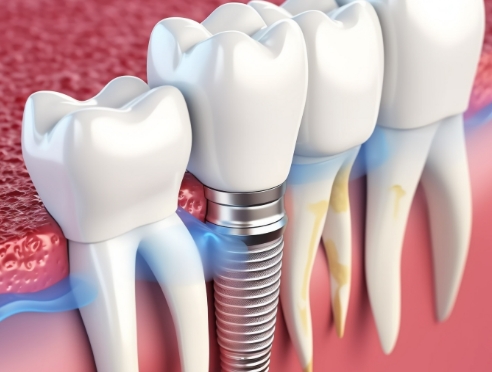

通过种植牙, 让您无忧进食, 自在微笑, 重拾生活的舒适感

种植牙是一项高难度治疗,

需依赖精密检查与充分的术前计划

因此, 选择具备丰富经验与专业技术的

医疗团队尤为重要